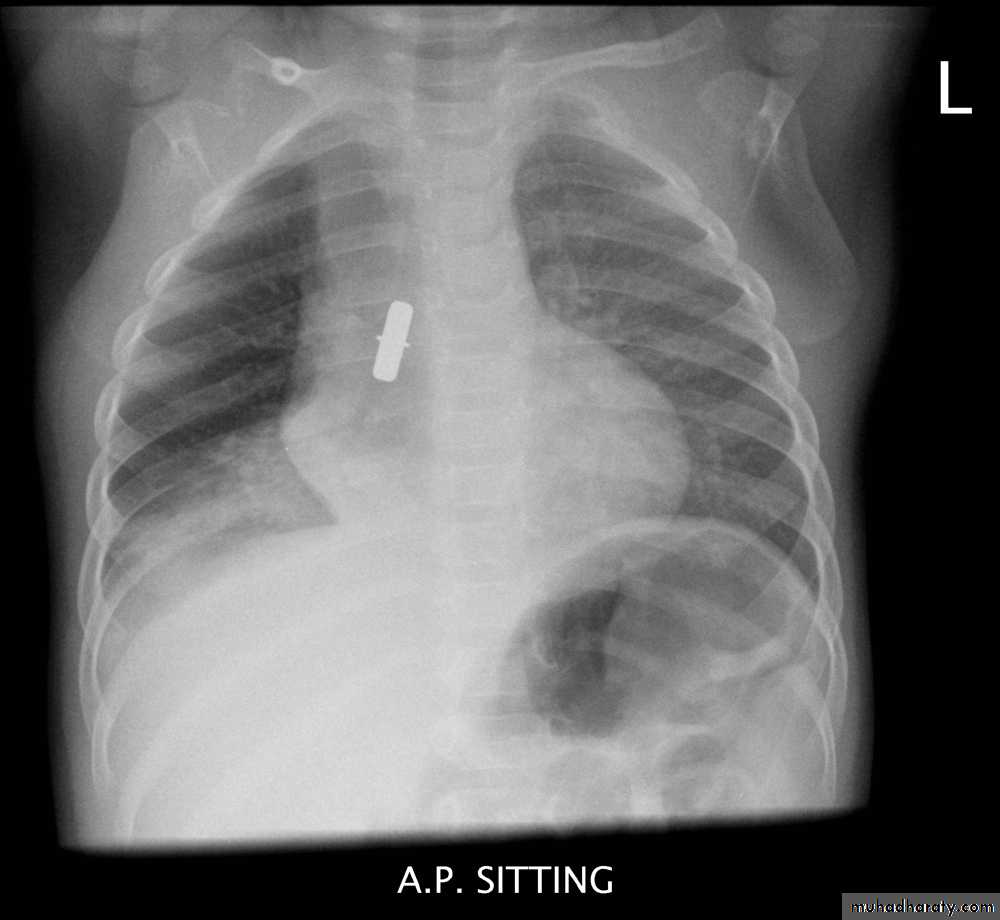

Foreign Body Inhalation

A common problem

Most common site for foreign body inhalation is?Clinical presentation:

• Asymptomatic only discovered by a witness• Stridor with dyspnea if stuck in the trachea or larynx

• wheezing with a persistent cough when in the bronchus

• repeated or persistent pneumonia with suppuration (late presentation).

Investigations:

Chest X-ray:

DDx: FB in the esophagus